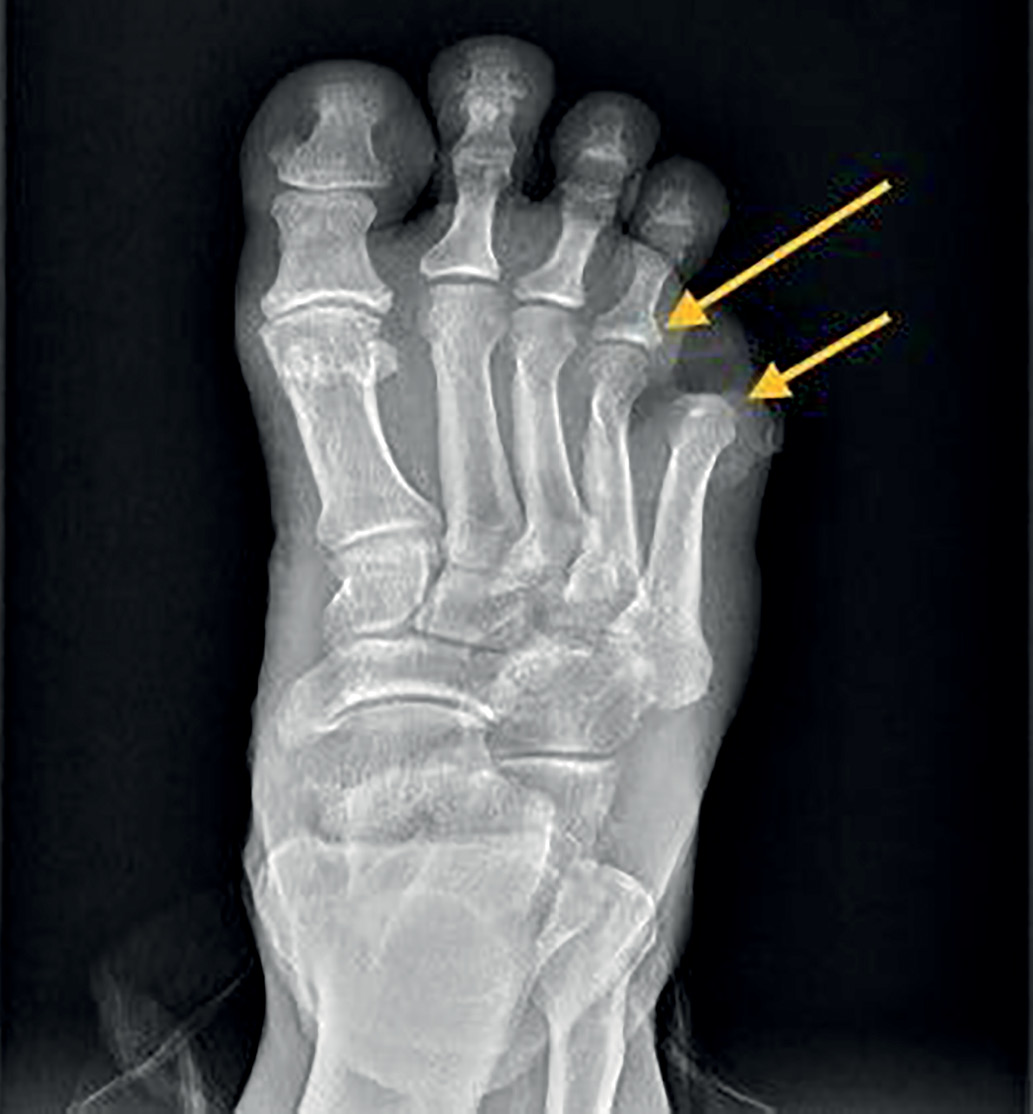

Status localis: кожа стоп теплая, сухая. Правая стопа умеренно отечна. Пульсация на артериях стоп справа снижена, слева сохранена. По данным УЗДГ: кровоток по a. dorsalis pedis — коллатеральный компенсированный, по a. tibialis posterior — магистрально-измененный. Вибрационная чувствительность справа и слева — на уровне тибиальной бугристости 0-1 УЕ, тактильная и температурная чувствительность отсутствуют, рефлекс Ахиллова сухожилия снижен. 5 палец ампутирован. Некротическая рана в передне-латеральной области стопы. В дне раны зондируются костные структуры, отделяемое гнойно-геморрагическое скудное. Поверхностная язва на тыльной поверхности 2 пальца правой стопы (рис. 1).

Рисунок 1. Внешний вид стопы при поступлении в стационар.

I.19.08.2022 г. выполнен первый этап хирургического лечения — экзартикуляция 4 пальца правой стопы, резекция головок 4, 5 плюсневых костей, хирургическая обработка раны. В послеоперационном периоде проводились системная антибактериальная терапия и ежедневные перевязки с антисептическими растворами, разгрузка правой стопы с помощью кресла-каталки (рис. 4).

Рисунок 4. Состояние после экзартикуляции 4 пальца правой стопы от 06.08.22 г.,

резекции головок 4 и 5 плюсневых костей от 19.08.22 г.